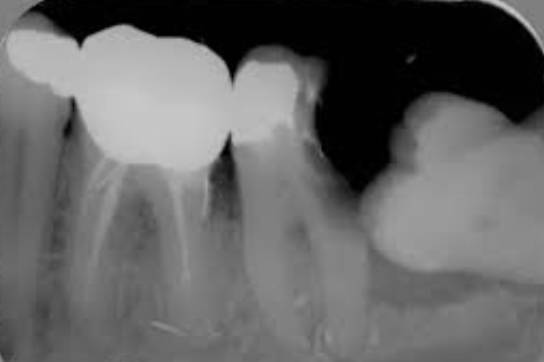

前倾阻生智齿,它的牙冠向前倾倒,直抵邻牙颈部,无论在口腔内还是X线片上都很直观,在形态上,跟警察跪压在黑人颈部非常相似,而且造成的后果也基本相同。

前倾智齿与邻牙形成一个敞开的间隙,经常会残留食物残渣,并且属于刷牙难以清理的死角,因此在邻牙邻面极易沉积菌斑,时间稍长即可形成邻面龋,龋损一旦攻破薄弱的牙骨质进入牙本质,邻牙即进入快速崩解毁灭期,于是产生临床上常见的“拔一送一”现象。

智齿顶坏了邻牙,一般都是因为疼痛剧烈而就诊,不是智齿痛而是邻牙痛,一般需要X线片进行确诊。临床根据邻牙龋损的深度,多半都是进行根管治疗或者拔除邻牙,但智齿本身大多是不治也不拔的,说实话,它真的像美国警察。

智齿顶着邻牙颈部的状况,是阻生智齿中产生危害最多的一种,临床上还有很多阻生智齿类型,前倾智齿冠部如果继续下倾,抵住牙颈部以下甚至牙根部位,乃至智齿全部埋伏在下颌骨内,那么产生危害不可预见,远不比肉眼可见的前倾智齿那么普遍。前倾智齿邻牙颈部菌斑导致龋坏是极大概率事件,而骨埋伏智齿只是可能形成“含牙囊肿”,或者因向前的生长潜力导致邻牙根破坏,它不存在菌斑因素,所以破坏没有那么直接,只能说风险客观存在,并且没有任何医生可以预测。